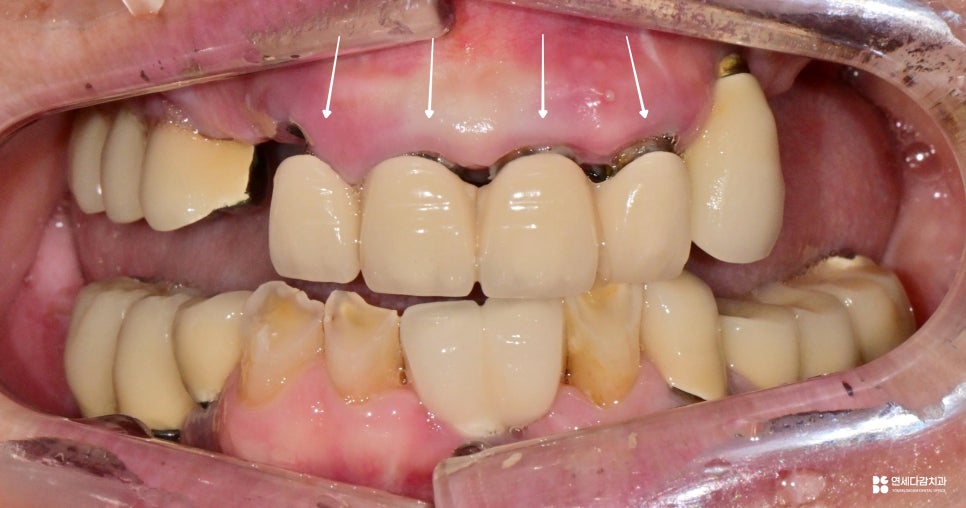

이 사진에서 제일 눈에 띄는 것은

잇몸이 상당히 내려가 있다는 점입니다.

앞니에는 보철이 수복되어 있는데

치근이 외부로 드러나 있고

그 안쪽으로는 충치까지 진행되었습니다.

또한 옆에 식립된 임플란트도 마찬가지로,

골소실이 굉장히 심각한 것으로 평가됩니다.

이러한 상황의 주요 원인은

바로 소홀한 청결 관리입니다.

치아와 잇몸 사이에 세균이 쌓이면

서서히 염증이 생기기 시작하고

염증은 뼈를 녹이는 작용을 합니다.

이렇게 한번 진료를 받은 부위라고 해서

관리를 소홀히 해도 되는 것은 아닙니다.

오히려 세균이 더 쉽게 쌓이는 구조라서

더욱 꼼꼼한 관리가 필요합니다.

임플란트 역시 마찬가지로

자연치처럼 충치가 생기는 것은 아니지만,

주변 잇몸 염증은 동일하게 나타날 수 있습니다.

특히 염증성 질환에 취약한 경향이 있어

더욱 주의가 필요하다는 것을 보여주는 사례입니다.